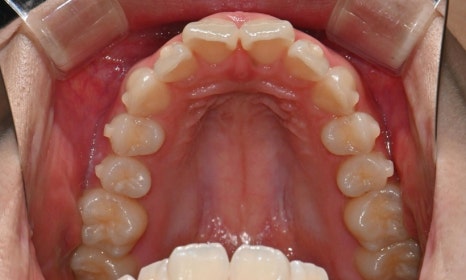

2025.3. 초진 (앞니 경미한 총생과 과개교합) - 연세정원치과

정밀진단 결과 위아래 앞니가 약간 겹쳐 있어 배열이 고르지 않은 상태였으며, 약간의 과개교합이 동반된 상태였습니다. 다만 골격적인 문제나 안모 불균형은 없었고, 측면에서도 돌출감 없이 비교적 안정적인 안모를 유지하고 있었습니다.

이번 케이스는 인비절라인 Comprehensive로 치료를 진행하였으며, 치아 이동은 과도하지 않게 단계적으로 진행하기 위해 치간삭제를 최소한으로 적용하며 공간을 확보하는 방향으로, 총 33단계의 장치를 통해 치아 이동을 계획하였습니다.

치료 후 전치부 배열이 정리되면서 웃을 때 스마일 라인도 한층 자연스럽게 개선되었습니다. 과개교합 역시 기능적으로 안정된 상태로 마무리할 수 있었습니다. 치료 후반부에 아주 경미한 중심선 차이가 남아 추가 장치를 통한 마무리를 권유드렸으나, 환자가 고2 학생으로 학업 일정이 바쁜 시기였고 현재 결과에 대해 본인과 보호자 모두 충분히 만족하여 이 상태에서 치료를 종료하기로 하였습니다.